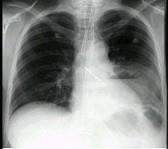

问题 女,36岁,发热,胸痛咳脓痰十余天,胸部正侧位如图,最可能的诊断为 ( )

选项 A.左下肺周围型肺癌并空洞形成 B.左下肺脓肿 C.左下肺空洞型肺结核 D.左侧包裹性液气胸 E.急性胃扩张

答案 B